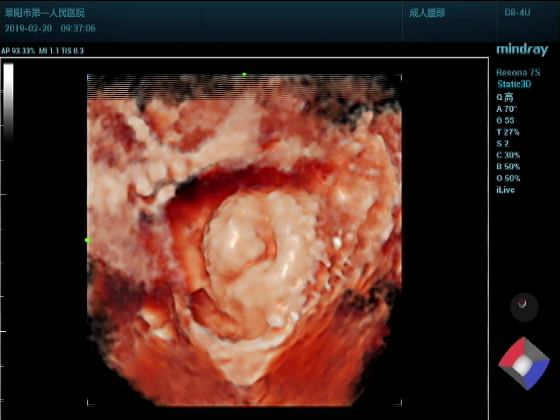

超声入门贴987--前列腺增大并膀胱结石(三维图)

男,75岁超声可见:前列腺明显增大,以内腺增大为主,内腺向膀胱内突入约2.17CM.实质回声尚均匀。膀胱腔内见弧线状强回声团,后伴声影,位置活动。

三维成像:前列腺向膀胱腔内呈“唇样“隆起,表面光滑。膀胱腔内结石团呈”蚕豆样“